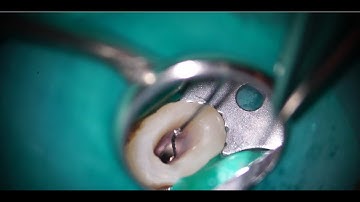

Removal of two long broken files with the Loop/長い破折器具二本をループで除去した症例